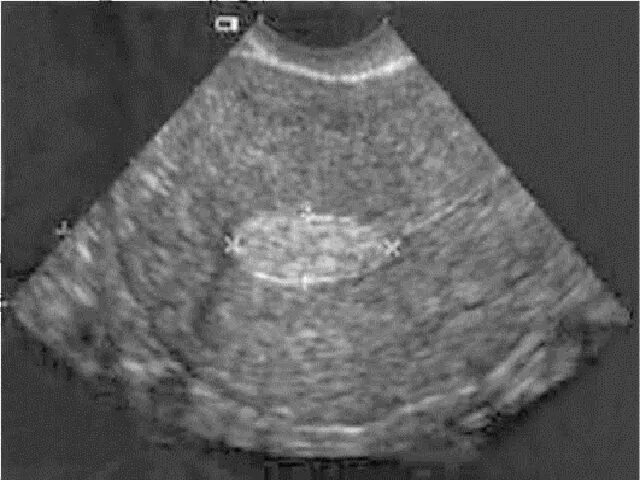

Как выглядит полип в матке на узи